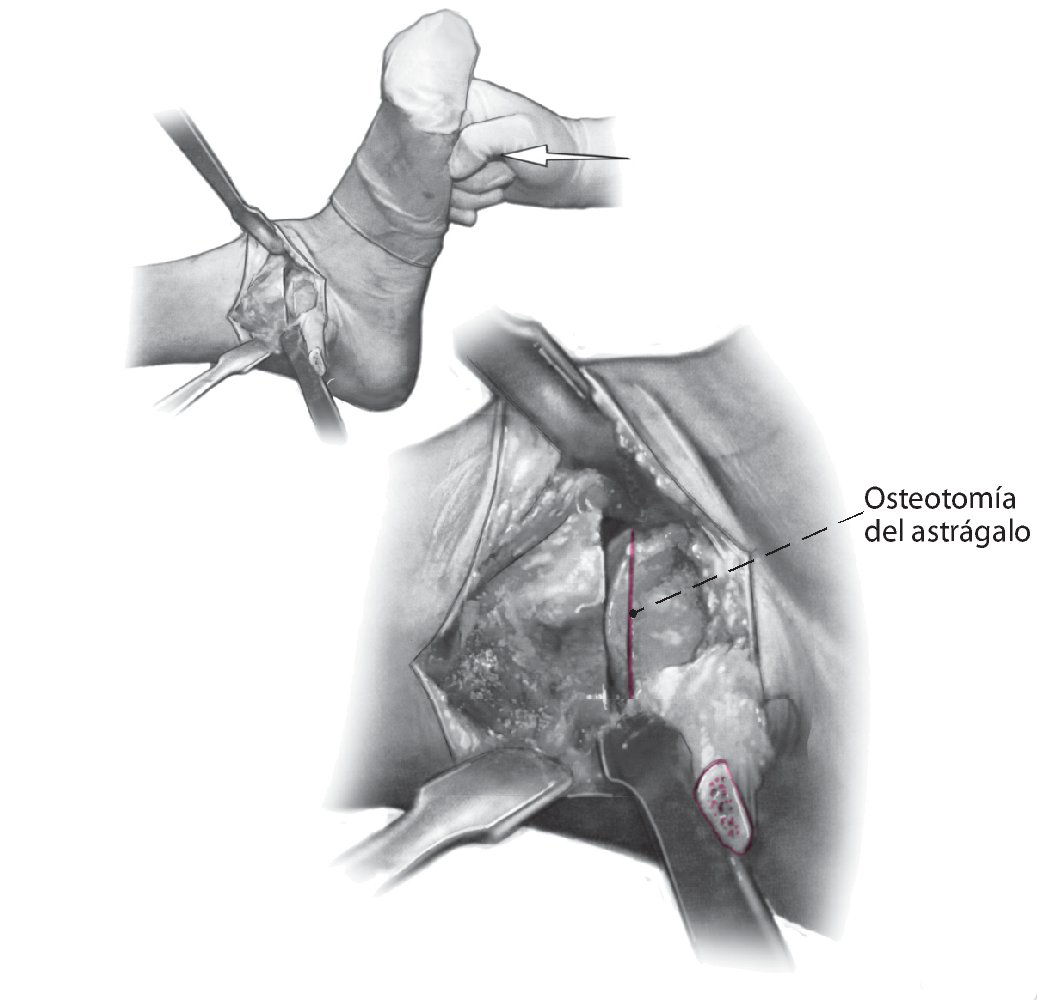

Fig. 7 Coloque el pie en la posición deseada usando el lado contralateral como plantilla. Plantígrado con 5-8º valgo y 5-15º de rotación externa. Cuando se haya identificado la posición deseada, se realiza una osteotomía sutil de la superficie superior del astrágalo de forma exactamente paralela a la osteotomía tibial.

Fig. 8 Compruebe la alineación apretando a la vez los cortes del astrágalo y de la tibia. Debe cuidarse la alineación neutra del retropié para que la altura sea idéntica en todas las direcciones.